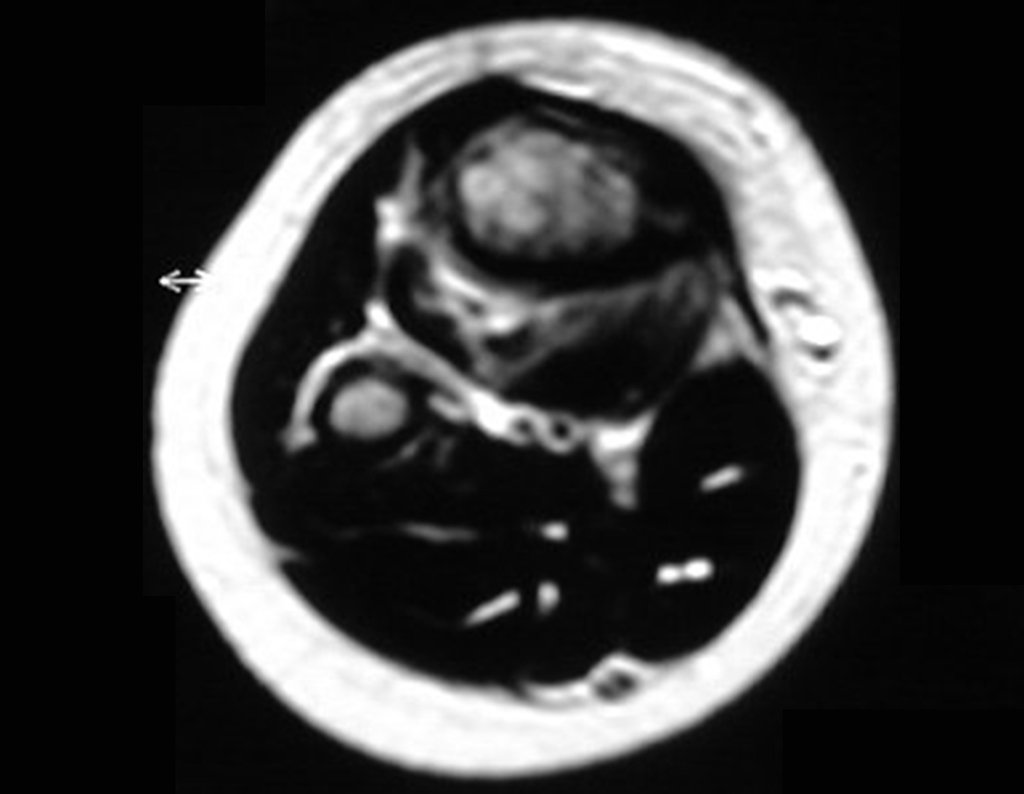

Ewing sarcoma of the tibia

In December 2006, the patient underwent surgery to resect the proximal metaphyseal segment of the tibia, including the growth plate, and self-transplantation of the growth cartilage of the proximal segment of the fibula, through transfer to the tibia, without microsurgery.